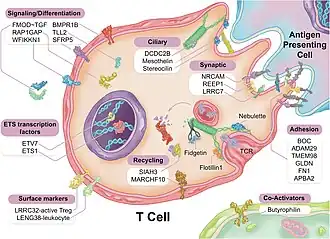

Several RNA Transcripts associated with CAD - FoxP1, ICOSLG, IKZF4/Eos, SMYD3, TRIM28, and TCF3/E2A are likely markers of regulatory T cells (Tregs), consistent with known reductions in Tregs in CAD.[55]

The RNA changes are mostly related to ciliary and endocytic transcripts, which in the circulating immune system would be related to the immune synapse.[56] One of the most differentially expressed genes, fibromodulin (FMOD), which is increased 2.8-fold in CAD, is found mainly in connective tissue[57] and is a modulator of the TGF-beta signaling pathway. However, not all RNA changes may be related to the immune synapse. For example, Nebulette, the most down-regulated transcript (2.4-fold), is found in cardiac muscle; it is a 'cytolinker' that connects actin and desmin to facilitate cytoskeletal function and vesicular movement. The endocytic pathway is further modulated by changes in tubulin, a key microtubule protein, and fidgetin, a tubulin-severing enzyme that is a marker for cardiovascular risk identified by genome-wide association study. Protein recycling would be modulated by changes in the proteasomal regulator SIAH3 and the ubiquitin ligase MARCHF10. On the ciliary aspect of the immune synapse, several of the modulated transcripts are related to ciliary length and function. Stereocilin is a partner to mesothelin, a related super-helical protein, whose transcript is also modulated in CAD. DCDC2, a double-cortin protein, modulates ciliary length. In the signaling pathways of the immune synapse, numerous transcripts are directly related to T-cell function and the control of differentiation. Butyrophilin is a co-regulator for T cell activation. Fibromodulin modulates the TGF-beta signaling pathway, a primary determinant of Tre differentiation. Further impact on the TGF-beta pathway is reflected in concurrent changes in the BMP receptor 1B RNA (BMPR1B), because the bone morphogenic proteins are members of the TGF-beta superfamily, and likewise impact Treg differentiation. Several of the transcripts (TMEM98, NRCAM, SFRP5, SHISA2) are elements of the Wnt signaling pathway, which is a major determinant of Treg differentiation.